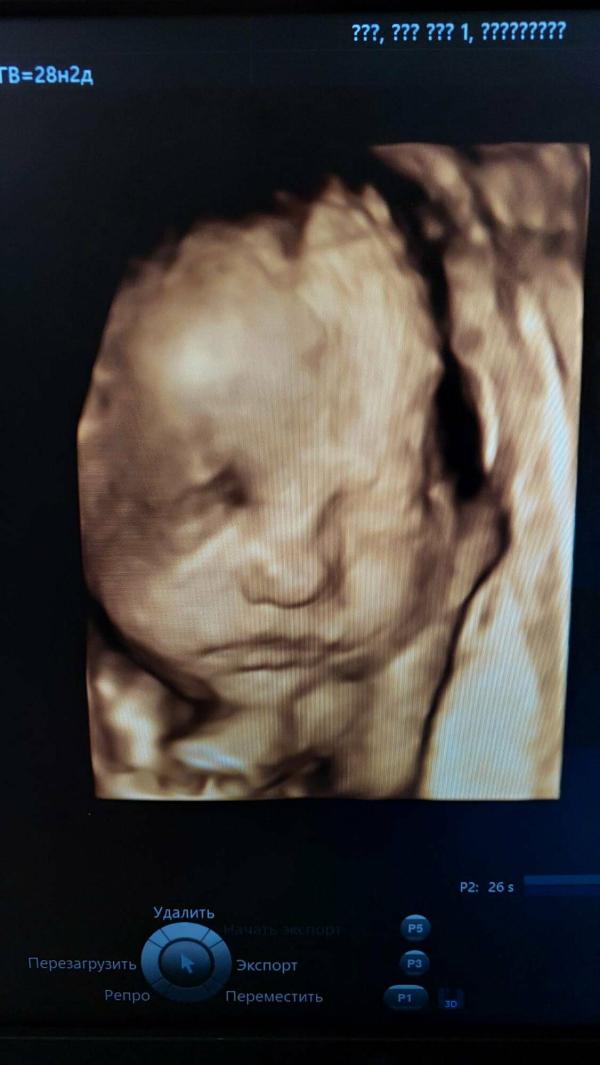

Почему- то в этот раз мы не опускали головку малышки прессом , как это было со средней дочерью, которую я тоже рожала с ГВ. Может быть потому что в этот раз было обвитие, я предупредила врача об этом ( знала, так как делала узи за день до родов). Мы перешли на кресло. И если со средней дочерью я потуг не запомнила, то тут пришлось поработать. Схватки даже на окситоцине так и были раз в 5 минут, чаще не становились, тужило слабо, сил не было, да и петля на шее доченьки заставляла внимательно слушать акушерку и тужиться только тогда, когда она разрешала. Сдерживать потуги было чуть ли не сложнее, чем тужиться по команде. Потуги затягивались, у нас было тугое обвитие, а дежурный неонатолог все не шёл. Был предпраздничный вечер и персонала было вообще не много . В итоге через 10 минут такого мучительного ожидания, акушерка Леночка сама рассекла пуповину на шее малышки и позволила мне , наконец, ее родить.